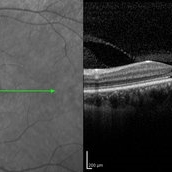

Optic Disc Drusen Optic Disc DrusenJul 10 2013 by Hamid Ahmadieh, MD SD-OCT image of the right eye of a 24-year-old woman with optic disc drusen and VA 20/20. Photographer: Solmaz Shahmohammadi, Negah Eye Center, Tehran Imaging device: Heidelberg Spectralis Condition/keywords: optic disc drusen, optical coherence tomography (OCT)